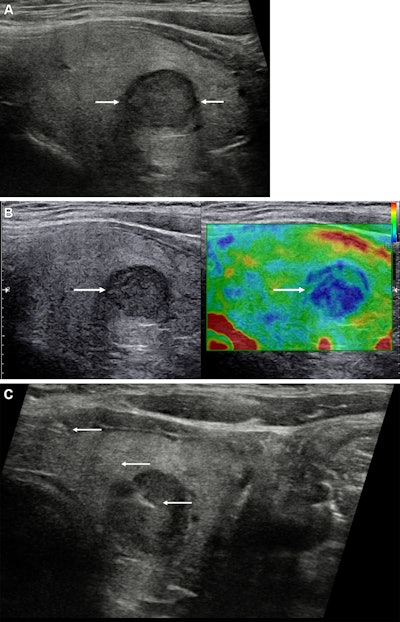

Images depict a 43-year-old woman with a solitary left-sided thyroid nodule classified at gray-scale ultrasound as category U3, upgraded to category U4 at strain elastography, and classified as category Thy4 at cytopathologic examination. Subsequent surgical histopathologic examination confirmed papillary cell carcinoma. (A) Longitudinal view of the left thyroid lobe demonstrates the low reflective nodule (between arrows) measuring 13 × 12 × 11 mm (not shown) and with a halo. (B) A longitudinal image with side-by-side visualization of the nodule (arrow) at gray scale (left) and strain elastography (right). The nodule is predominantly blue, indicating increased stiffness. (C) A longitudinal view shows the needle (arrows) within the stiffer aspect of the nodule for cytology sampling. U and Thy categories are according to British Thyroid Association system. Image courtesy of the RSNA.